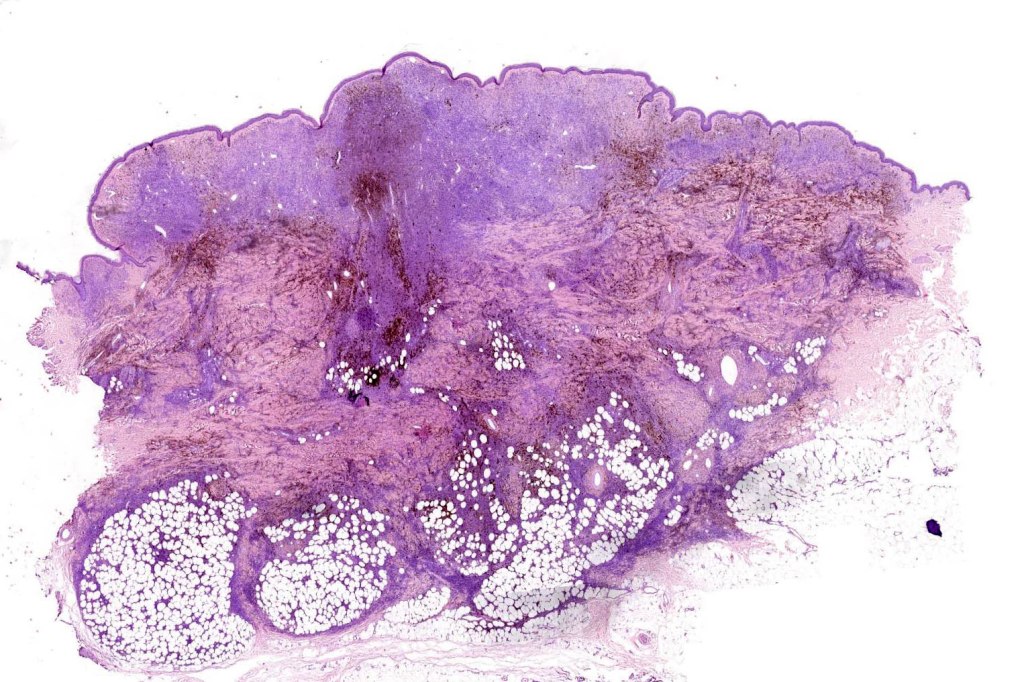

Combined common & deep penetrating nevus